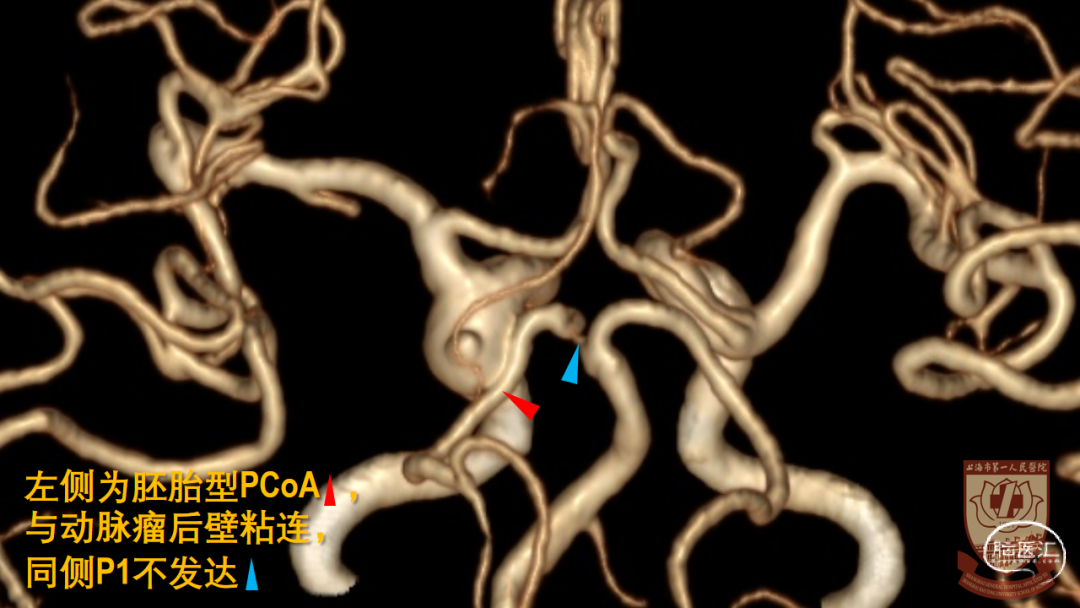

CTA:左侧大型后交通动脉瘤,指向后、外、下

大型动脉瘤,形态复杂:发自ICA后外壁,宽颈、后交通动脉自瘤颈发出

胚胎型后交通动脉,必须保留

窗式夹可用于后壁宽颈动脉瘤

窗式夹释放较困难,不利于保护ICA后、内侧壁发出的穿支